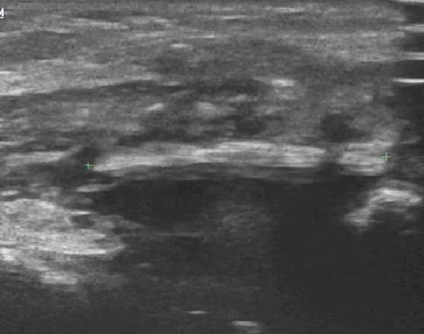

УЗИ.

Метод высоко чувствителен в т.ч для выявления рентгеннегативных инородных тел. Характерно наличие вблизи них свободной жидкости или осумкованных жидкостных скоплений, инфильтрации окружающих тканей. Доплерография выявляет отсутствие кровотока внутри выявленного инородного тела. Но трудности метода УЗИ в выявлнии глубоко расположенных инородных тел и расположенных позади газосодержащих полых органов.